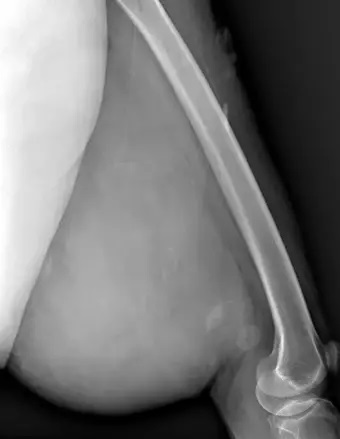

Mardin’de yaşayan H.T. (42), 3 yıl önce sağ baldırının arka kısmında oluşan ve başlangıçta yumurta büyüklüğünde olan kitlenin zamanla büyümesi üzerine Dicle Üniversitesi Tıp Fakültesi Hastanesi Ortopedi ve Travmatoloji Bölümü’ne başvurdu.

Muayenede yumuşak doku kitlesi olduğu değerlendirilen şişliğin alınması için Ortopedi ve Travmatoloji Anabilim Dalı Öğretim Üyesi Prof. Dr. Emin Özkul ve ekibi tarafından ameliyat kararı verildi. Yaklaşık 2 saat süren operasyonla kitlenin çıkarıldığı, kitlenin 5 kilo 668 gram geldiği belirtildi.

Bu hasta da 3 yıl önce fark edilmiş küçük bir kitle, zamanla çok büyük boyutlara, yaklaşık 6 kiloya varan boyutlara varmıştı. Neredeyse bütün bacak boyu yayılan bir kitlesi mevcuttu.